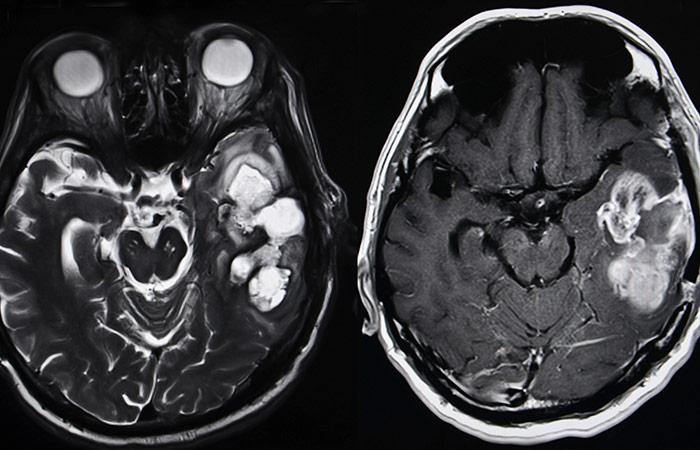

3. And This Is What A Brain Tumor Looks Like

Whenever we hear someone being afflicted with conditions such as brain hemorrhage or a brain tumor, we don’t actually know what exactly is happening to their body or that particular organ. A tumor is a condition in which the cells of our body keep multiplying, even though the body doesn’t need new ones. However, our brain is enclosed by our skull, where the space is very limited so a tumor puts extra pressure on the brain (2).